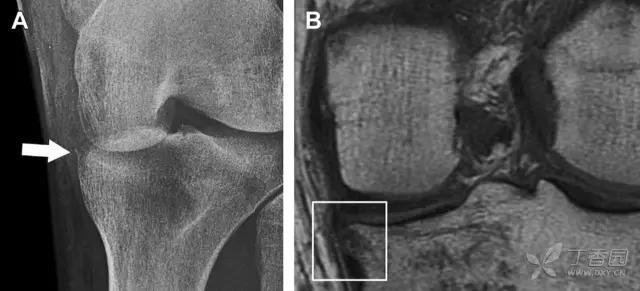

9 股骨外侧髁凹陷征

图 2 扭伤后的股骨外侧髁凹陷征

A 侧位片示股骨外侧髁凹陷。B MRI 矢状位 T2 加权像示股骨外侧髁及胫骨后外侧骨挫伤(空箭头)。胫骨近端随着后交叉韧带撕裂发生移位,露出外侧半月板的后角(弧形箭头)。